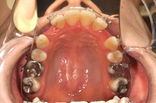

叢生

主訴:叢生

年齢:16y1m

診断:叢生・4┴4/4┬4抜歯

装置・期間:上顎急速拡大装置・上顎クアッドヘリックス・上下顎マルチブラケット装置 4年2カ月間(16y1m~20y3m)

保定 上下顎保定装置 2年間以上

抜歯部位:上下顎第一小臼歯4本

治療費:矯正基本料800,000円+クリアブラケット30,000円+処置料3,000~6,000円×54回(別途消費税)

保定装置料50,000円(別途消費税)